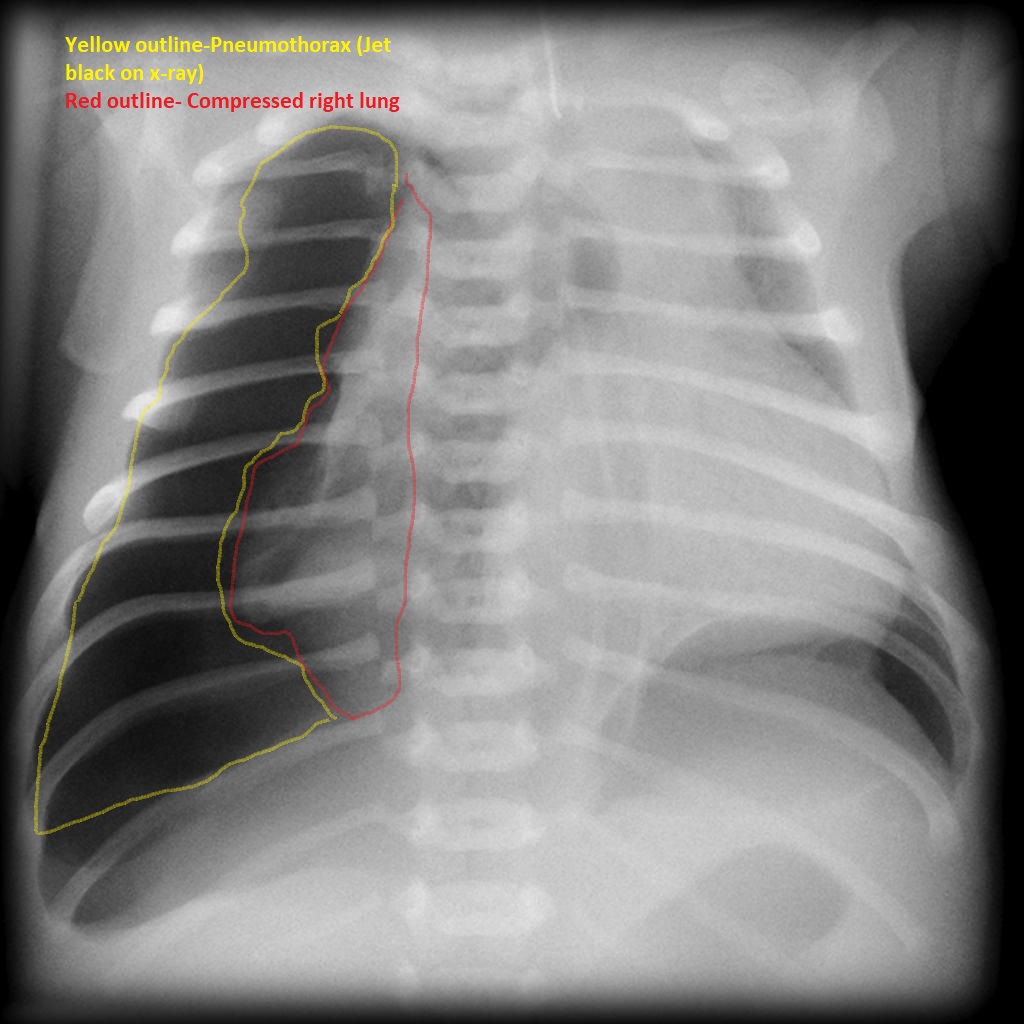

Pneumothorax

Feature Description

Visceral pleural line Thin sharp white line marking the lung edge, separated from chest wall.

Absence of lung markings No pulmonary vascular markings peripheral to the visceral pleural line.

Deep sulcus sign In supine films, abnormally deep and lucent costophrenic angle suggesting an anterior pneumothorax.

Right-sided pneumothorax